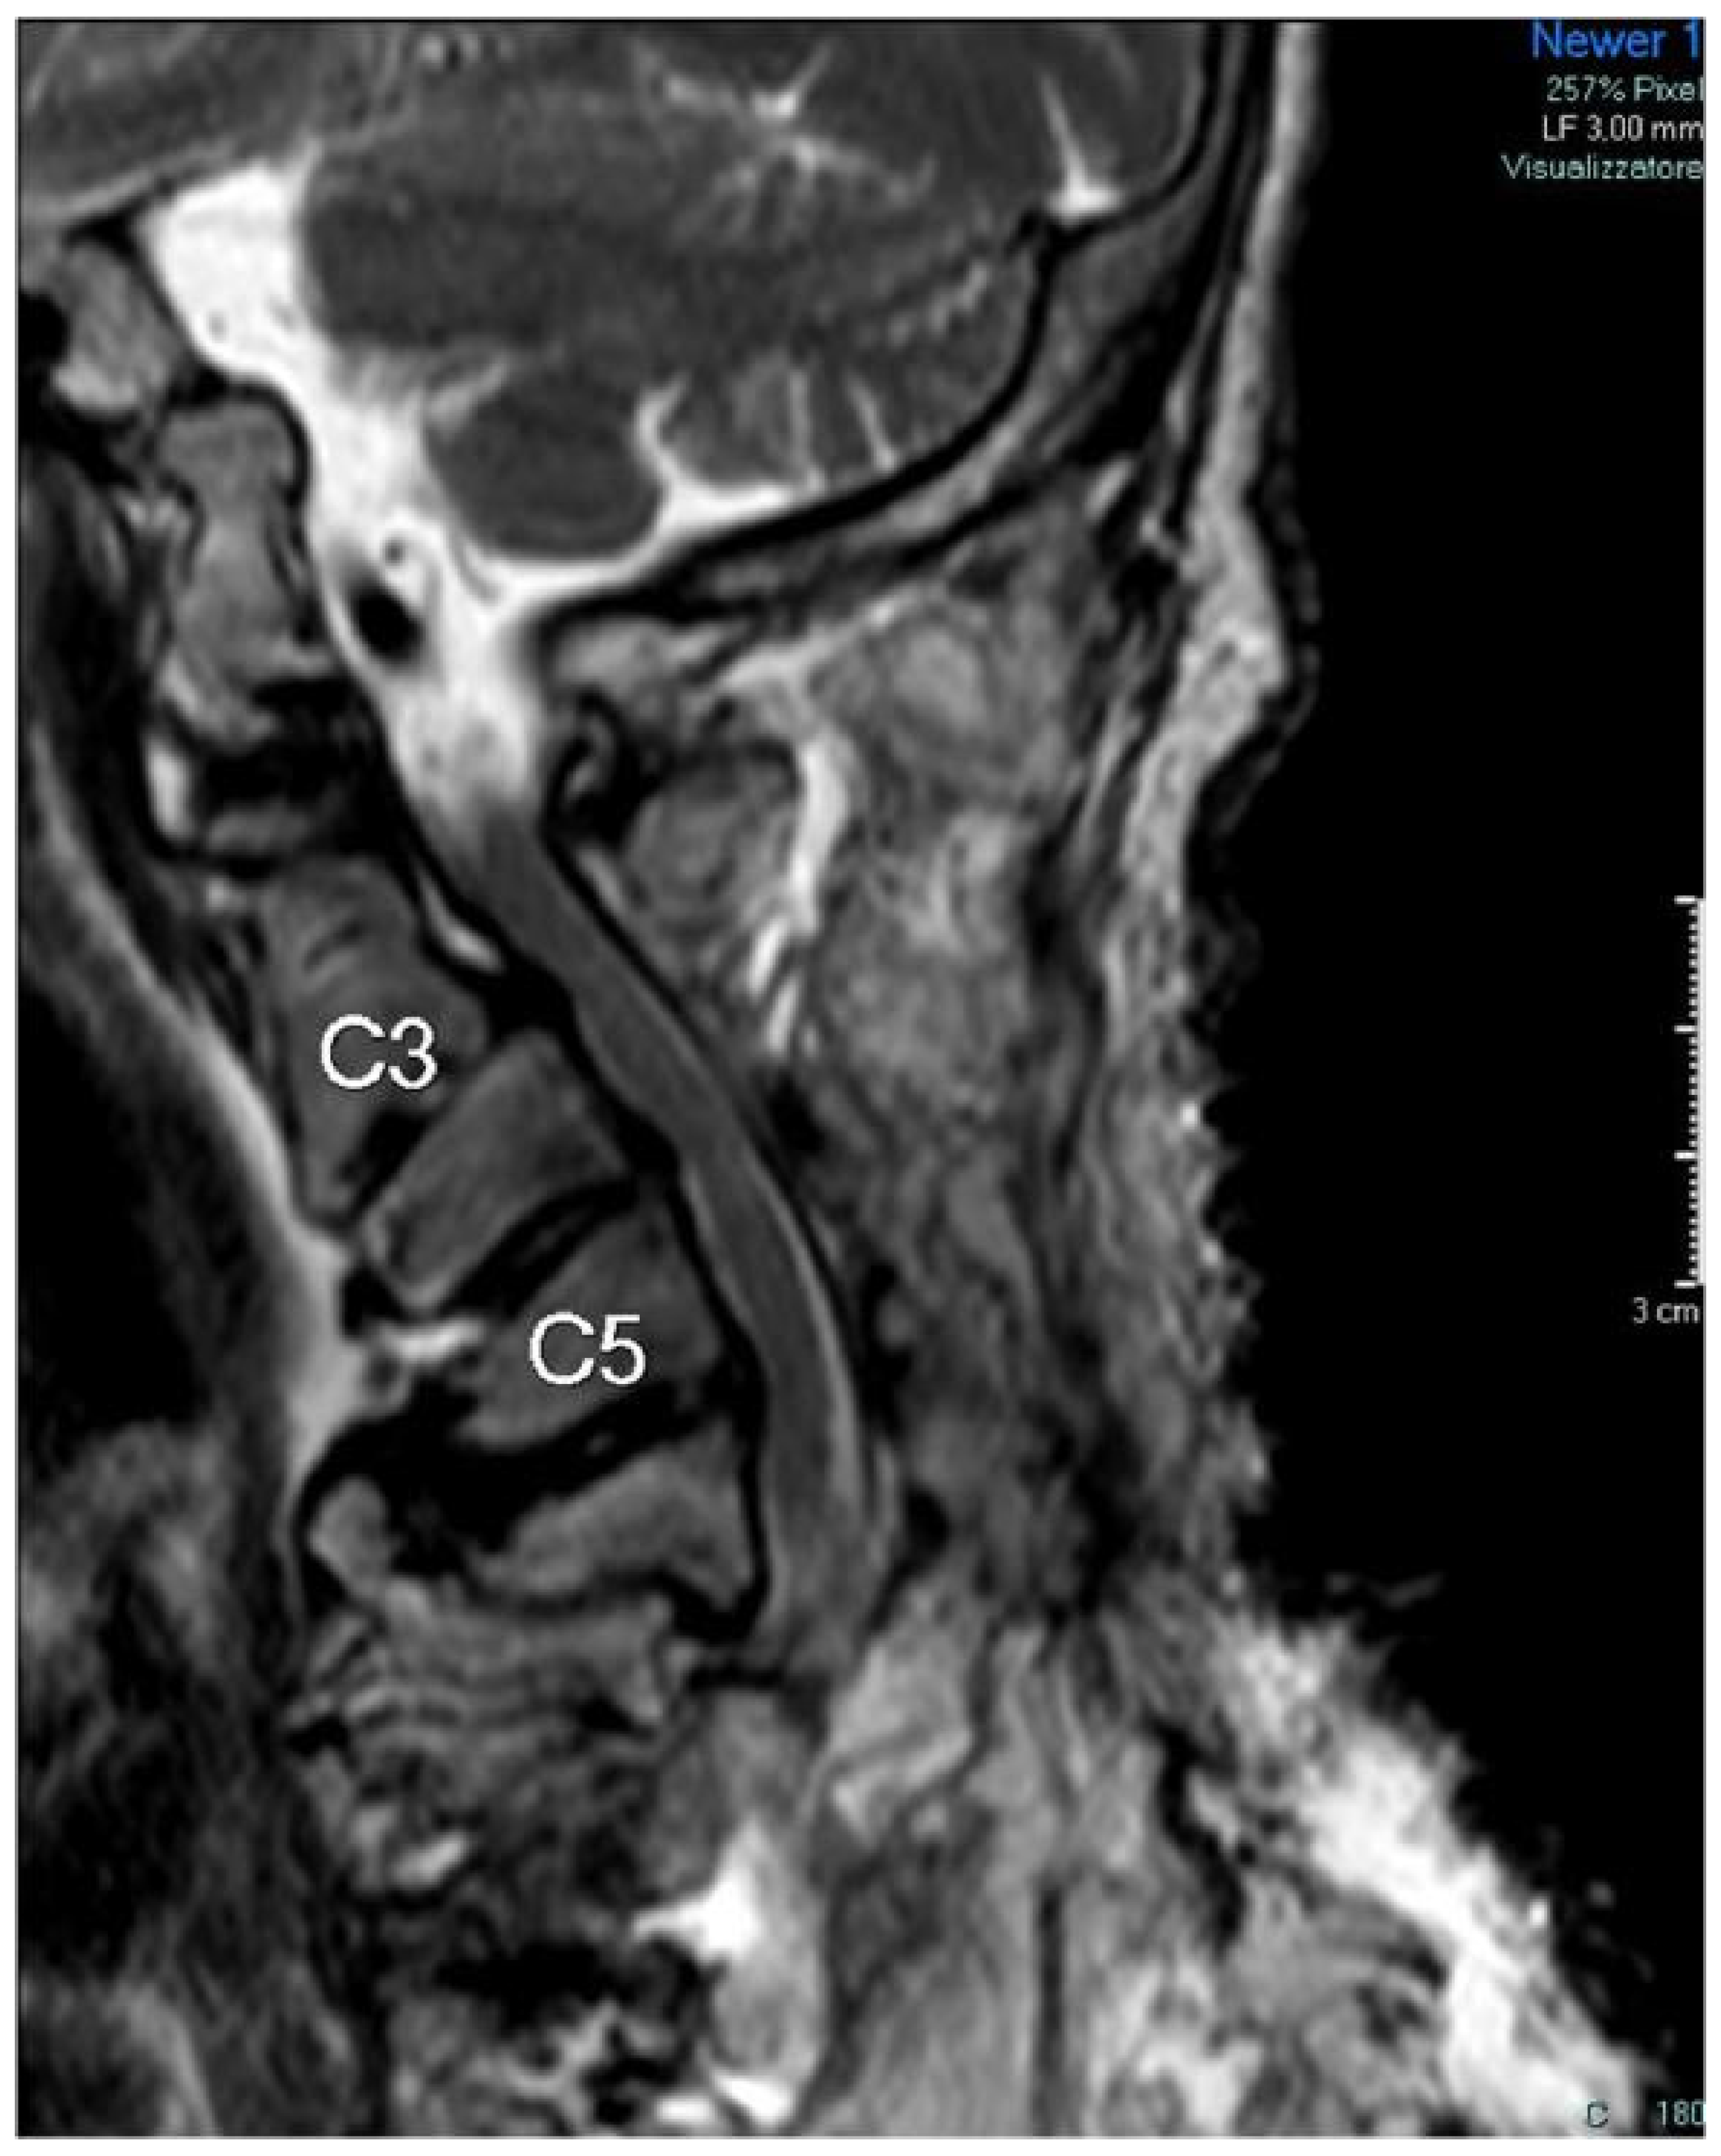

5. Follow-Up Control